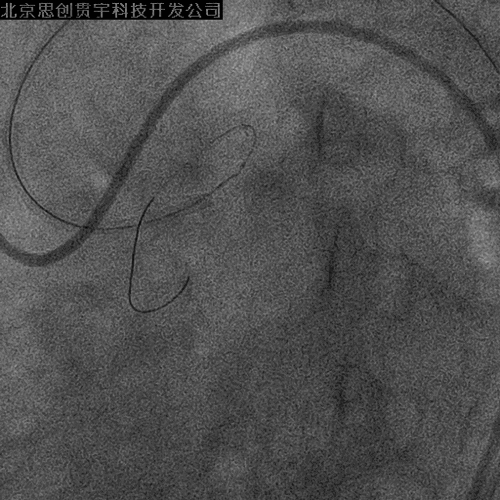

CAG

LM闭塞

RCA粗大,大量左向右侧枝形成

PCI-LAD

双侧股动脉

7F XB3.5指引; Pilot 150导丝;Finecross 130cm MG

左冠PCI

Culotte技术

LAD—Resolute 3.0*30mm

LM-LCX—Resolute 3.0*30mm

LM-LAD—+Resolute 3.5*30mm